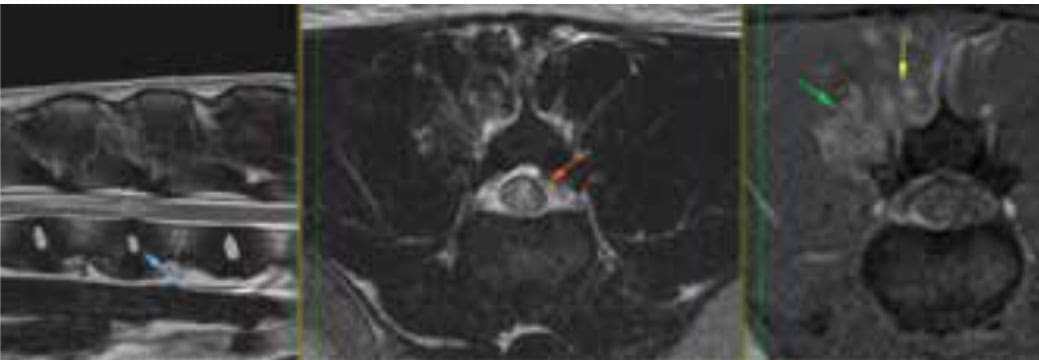

MRI is usually preferable in cases with spinal cord lesions, where availability and finances allow. Plain CT and CT myelogram can be utilised successfully in many acute disc extrusions to identify site and side. However, MRI may be necessary in cases where CT fails to identify the pathology and is more sensitive for cord pathology or for differentiating non-compressive lesions. MRI is preferable to identify disc protrusions, soft tissue tumours and intraparenchymal lesions such as acute non-compressive nucleus pulposus extrusion (ANNPE or hit and run disc) – see Figure 3, meningomyelitis or syringomyelia.

Figure 3. MRI performed in a one-year old Labrador with peracute-onset hindlimb paralysis. This patient had suffered a type 3 or ‘hit and run’ disc extrusion (acute non-compressive nucleus pulposus extrusion/ANNPE) at L1-2, with extensive spinal cord damage. CT myelogram would have offered a diagnosis of ‘non-compressive/nonsurgical lesion’ and would not have identified the specific type or extent of lesion in this case.